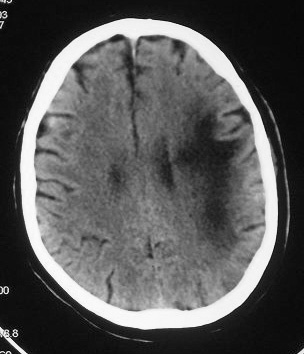

This is the MRI from an Immunocompromised Pt. What is the DDX?

Progressive Multifocal Leukoencephalopathy (PML)

CT

- Asymmetric focal zones of low attenuation involving the peri-ventricular and sub-cortical white matter.

MRI

- Multifocal, asymmetric peri-ventricular and sub-cortical involvement.

- There is little or no mass effect.

- T1: Usually hypo-intense

- T2 : HYPER-intense

- T1 C+ (Gd) : typically NO enhancement, however if present it may be associated with improved survival